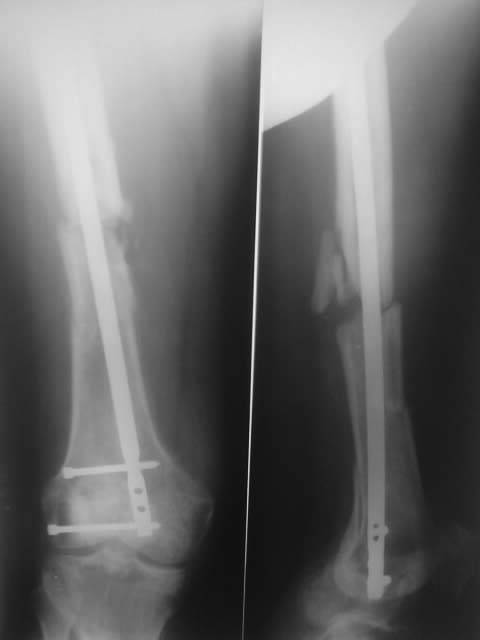

Был меж вертельный и оскольчатый перелом бедра, сделали остеосинтез,прошло 5 месяцев,не сращение.предлагают убрать нижний болт и сделать пластику.на что согласиться?

На мой взгляд, представленный план неоптимален, и может создать больше проблем, чем решить.

Стержень тонкий, на уровне нижнего перелома нестабильность, в этих условихя пластику делать бесперспективно - из-за подвижности не прорастут сосуды, соответственно, не приживет трансплантат.

И при закрытом интрамедуллярном остеосинтезе вообще пластики делать ни к чему. Здесь нужно убрать этот гвоздь, рассверлить канал и ввести гвоздь больше диаметром. И заереть его внизу понадежнее, винтами большего диаметра и не короткими, как сейчас. Вверху - динамически и с компрессией. Тут же можно будет ходить без ограничения нагрузки.

Удаление нижнего винта вряд ли тут решит проблему, он и так не сильно что-то держит. Тут еще можно было бы подумать про введение винтов вплотную к гвоздю для искусственного сужения канала. Но надежнее поменять гвоздь, поверьте.